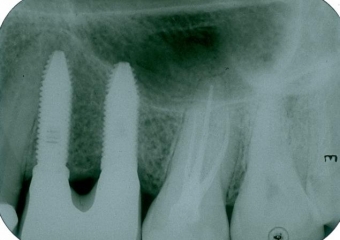

Rx mostrando a ausência de dois pré molares superiores

Raio X dos implantes instalados